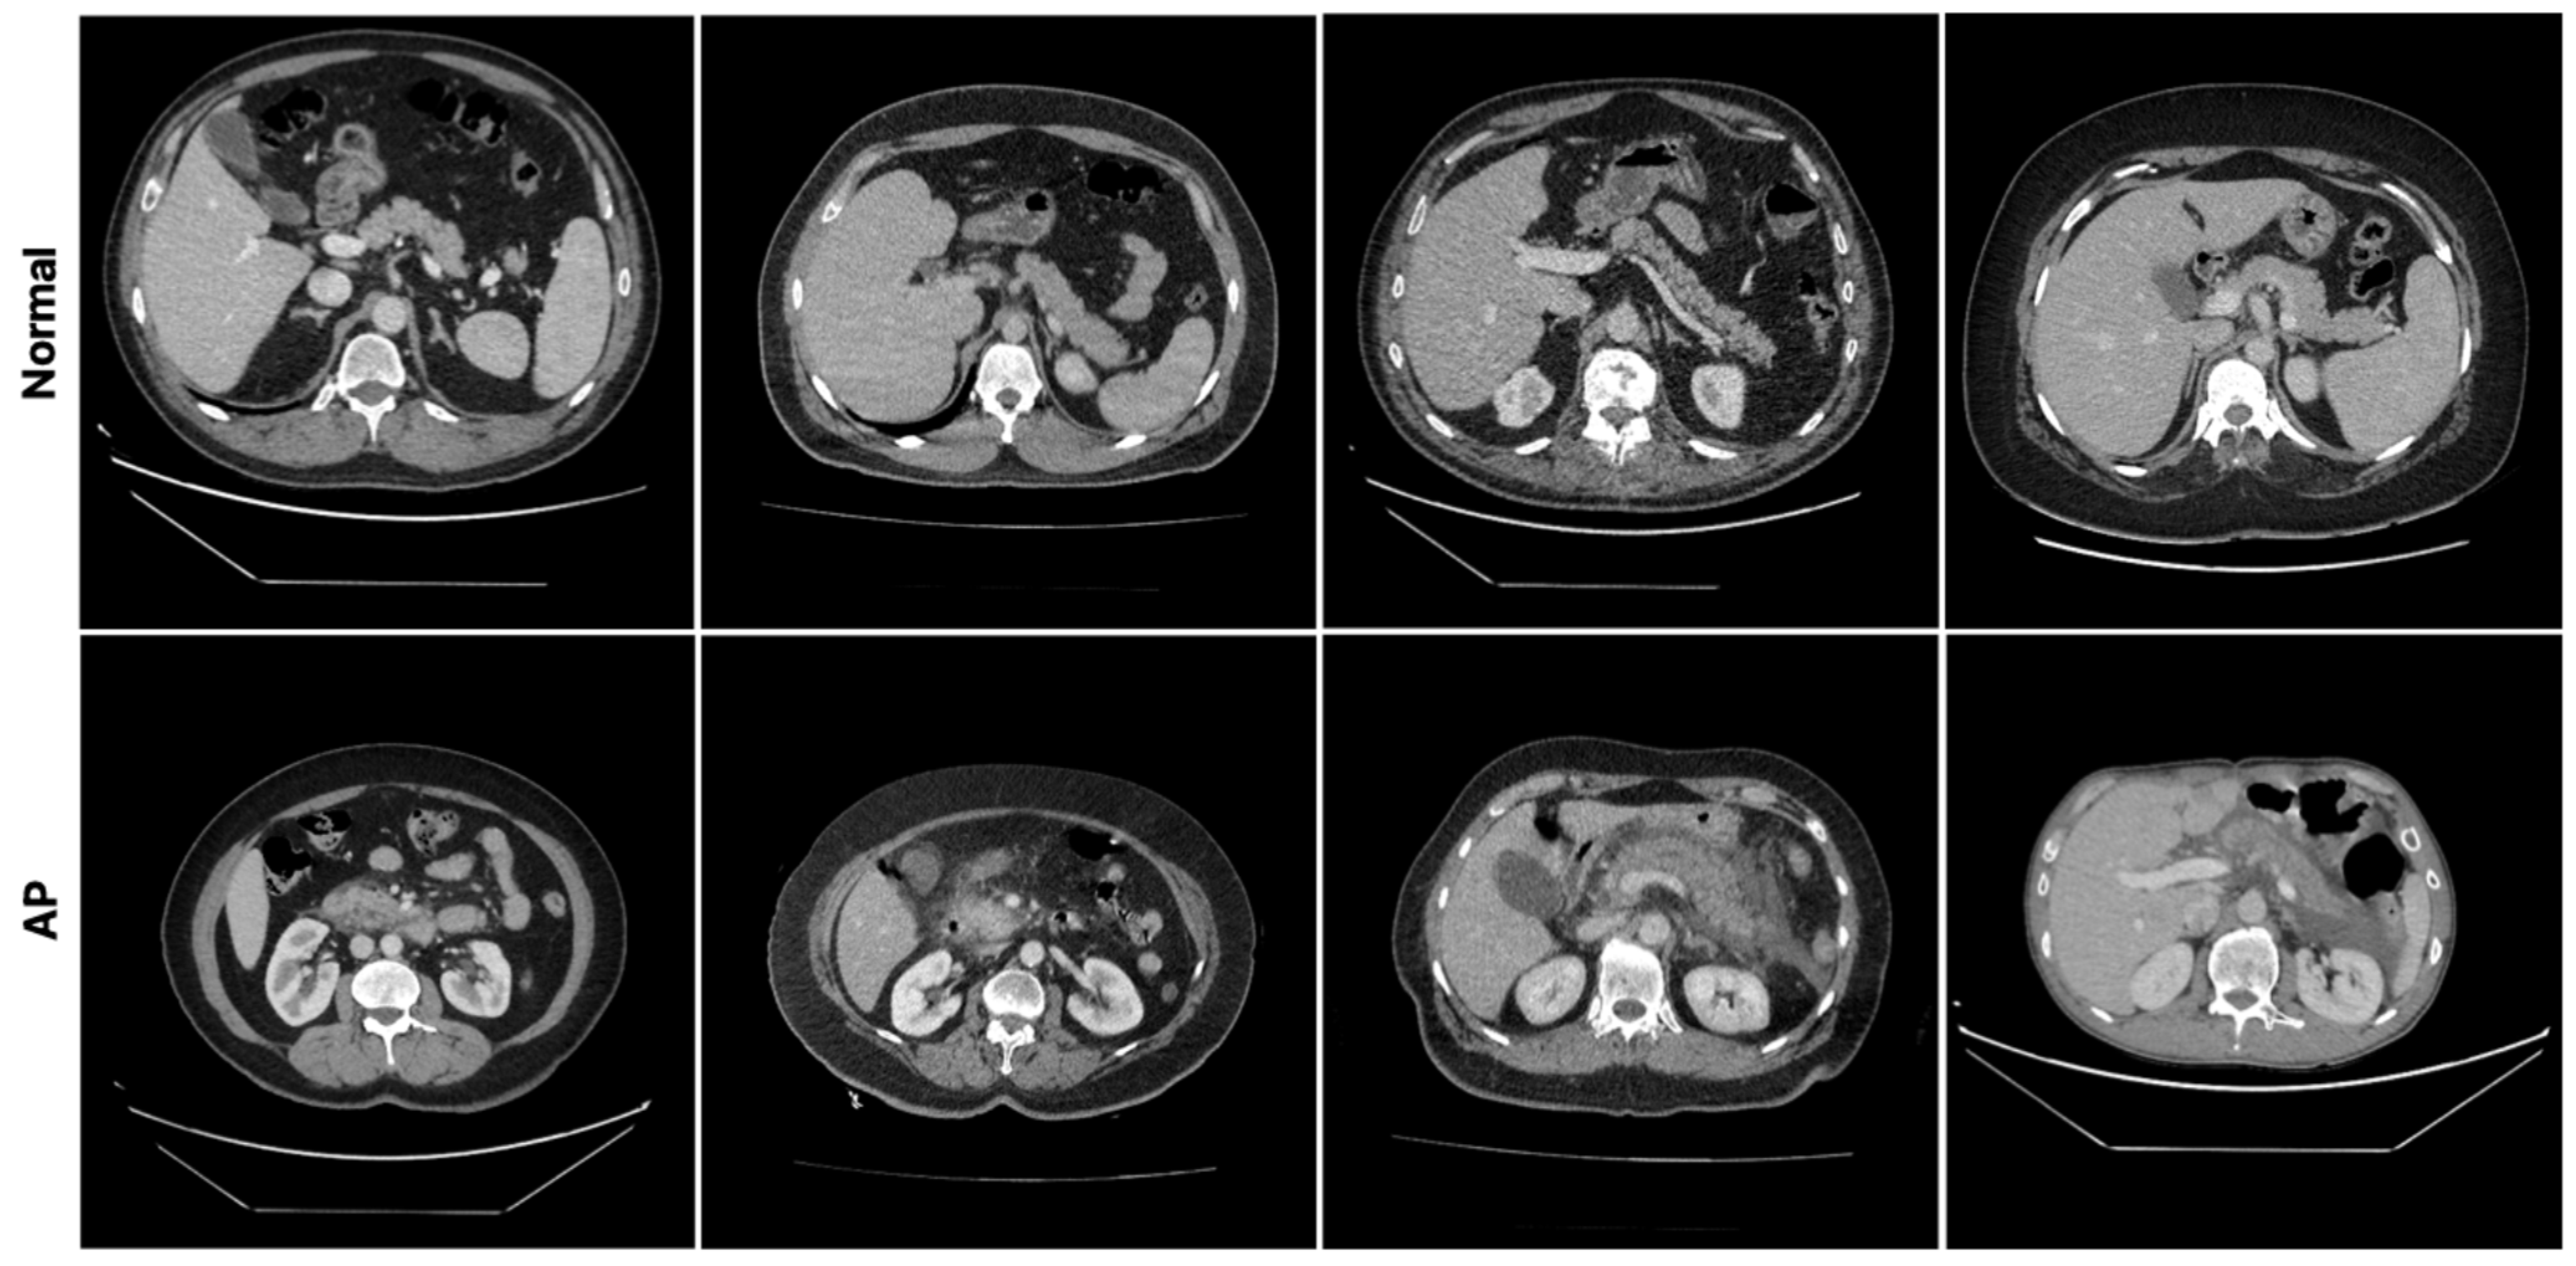

3]. A normal (healthy) pancreas is typically seen on CT as a structure with homogeneous soft tissue density, smooth contours, and relatively heterogeneous contrast enhancement [

4]. However, its morphology and density characteristics may vary depending on patient-related factors and the imaging phase. Pathological processes affecting the pancreas often cause changes in its CT appearance, such as focal or diffuse enlargement, irregular contours, heterogeneous density, and involvement of adjacent tissues [

5]. In particular, inflammatory conditions may be accompanied by increased density and heterogeneity of peripancreatic adipose tissue, fluid collections, vascular complications, and parenchymal heterogeneity. These findings are the basis for radiological evaluations in clinical practice [

The pancreatic dataset, which was created specifically for this study, was generated from CT images of patients with AP and normal pancreatic tissue. The dataset contains CT images from 183 patients, 103 of whom are in the normal group and 80 of whom are in the AP group. At the beginning of the data preparation process, the patients were divided into two classes according to their clinical diagnoses: normal and AP. The appearance of pancreatic tissue can be influenced by CT acquisition protocols and contrast enhancement phases, not only due to pathology, but also due to imaging conditions. In our dataset, CT scans were acquired under routine clinical conditions. Therefore, images obtained using different contrast enhancement phases may be included in both normal and AP cases. The image windowing parameters were set to a window width (WW) of 400 and a window level (WL) of 50 to ensure optimal contrast and visibility of the pancreatic tissue. These settings allow for more distinct visualization of the pancreatic parenchyma and surrounding anatomical structures, highlighting the model’s features. To prevent slice-level from the same patient from appearing in both the training and test sets and to reliably evaluate the model’s generalization ability, the dataset was split into training and test sets on a patient-by-patient basis. To avoid analyzing anatomical regions that could affect classification performance, only slices with clearly visible pancreatic tissue were selected for the analysis.